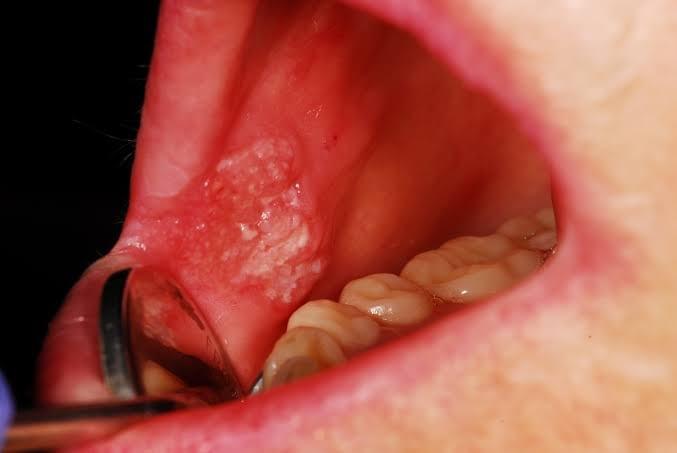

- Oral Cancer - Oral Cancer can appear as various forms: - A painless ulcer that doesn't heal >3 weeks,

- A slow growing granular swelling,

- Rough crusts/eroded area on the lips, &

- White/red patches in your mouth.

- Risk factors of oral cancer include smoking, excessive exposure to sunlight, excessive alcohol consumption, chewing of tobacco and paan (betel leaf with Areca nut), HIV etc. - Do not put yourself into unnecessary risk! Contact your dental practitioner and get a dental check-up regularly for cancer screening. - *Oral cancer assessment requires specific clinical procedures such as a biopsy, and cannot be confirmed by just visual screening.